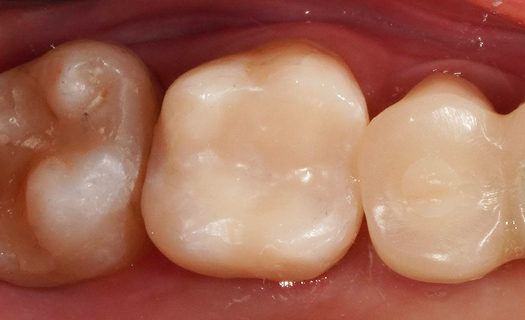

Перелечивание зуба с кистой под микроскопом

Проблема: У пациента отек щеки, боли самопроизвольные, усиливающиеся при приеме пищи, неудачное первичное лечение зуба (старыми методами).

Лечение: Проведено эндодонтическое перелечивание зуба под дентальным микроскопом, что позволило точно выявить анатомические особенности корневых каналов и устранить последствия ранее некачественного лечения. После купирования воспалительного процесса (киста) каналы герметично запломбированы. Коронковая часть зуба восстановлена для сохранения функции и герметичности до этапа постоянного протезирования.

Результат: После проведённого лечения болевые ощущения полностью устранены, отёк щеки исчез, воспалительный процесс купирован. Зуб сохранён, восстановлена его функция. Установлена коронка, что позволило полностью восстановить анатомическую форму и жевательную эффективность зуба.